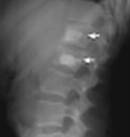

| Bodies | Height, trabeculations |

| Disks | Height, |

| Odontoid | #'s, dens-anterior arch distance (adults: < 3 mm; peds: < 5 mm) |

| Lines | Anterior spinal line, posterior spinal line, spinolaminar line, clivus base line |

| Lordosis | |

| Soft tissue swelling | Retropharyngeal, retroesophageal |

| Degenerative disk disease (DDD) | ↓ disk space osteophytes borders of adjac vert bodies may vacuum phen |